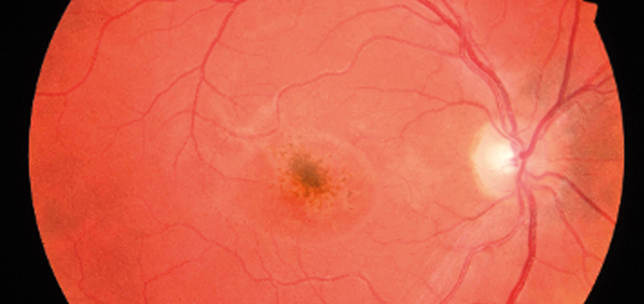

A unique case of macular burn from ‘toy’ laser

Paras Agarwal

Manoj Kulshrestha